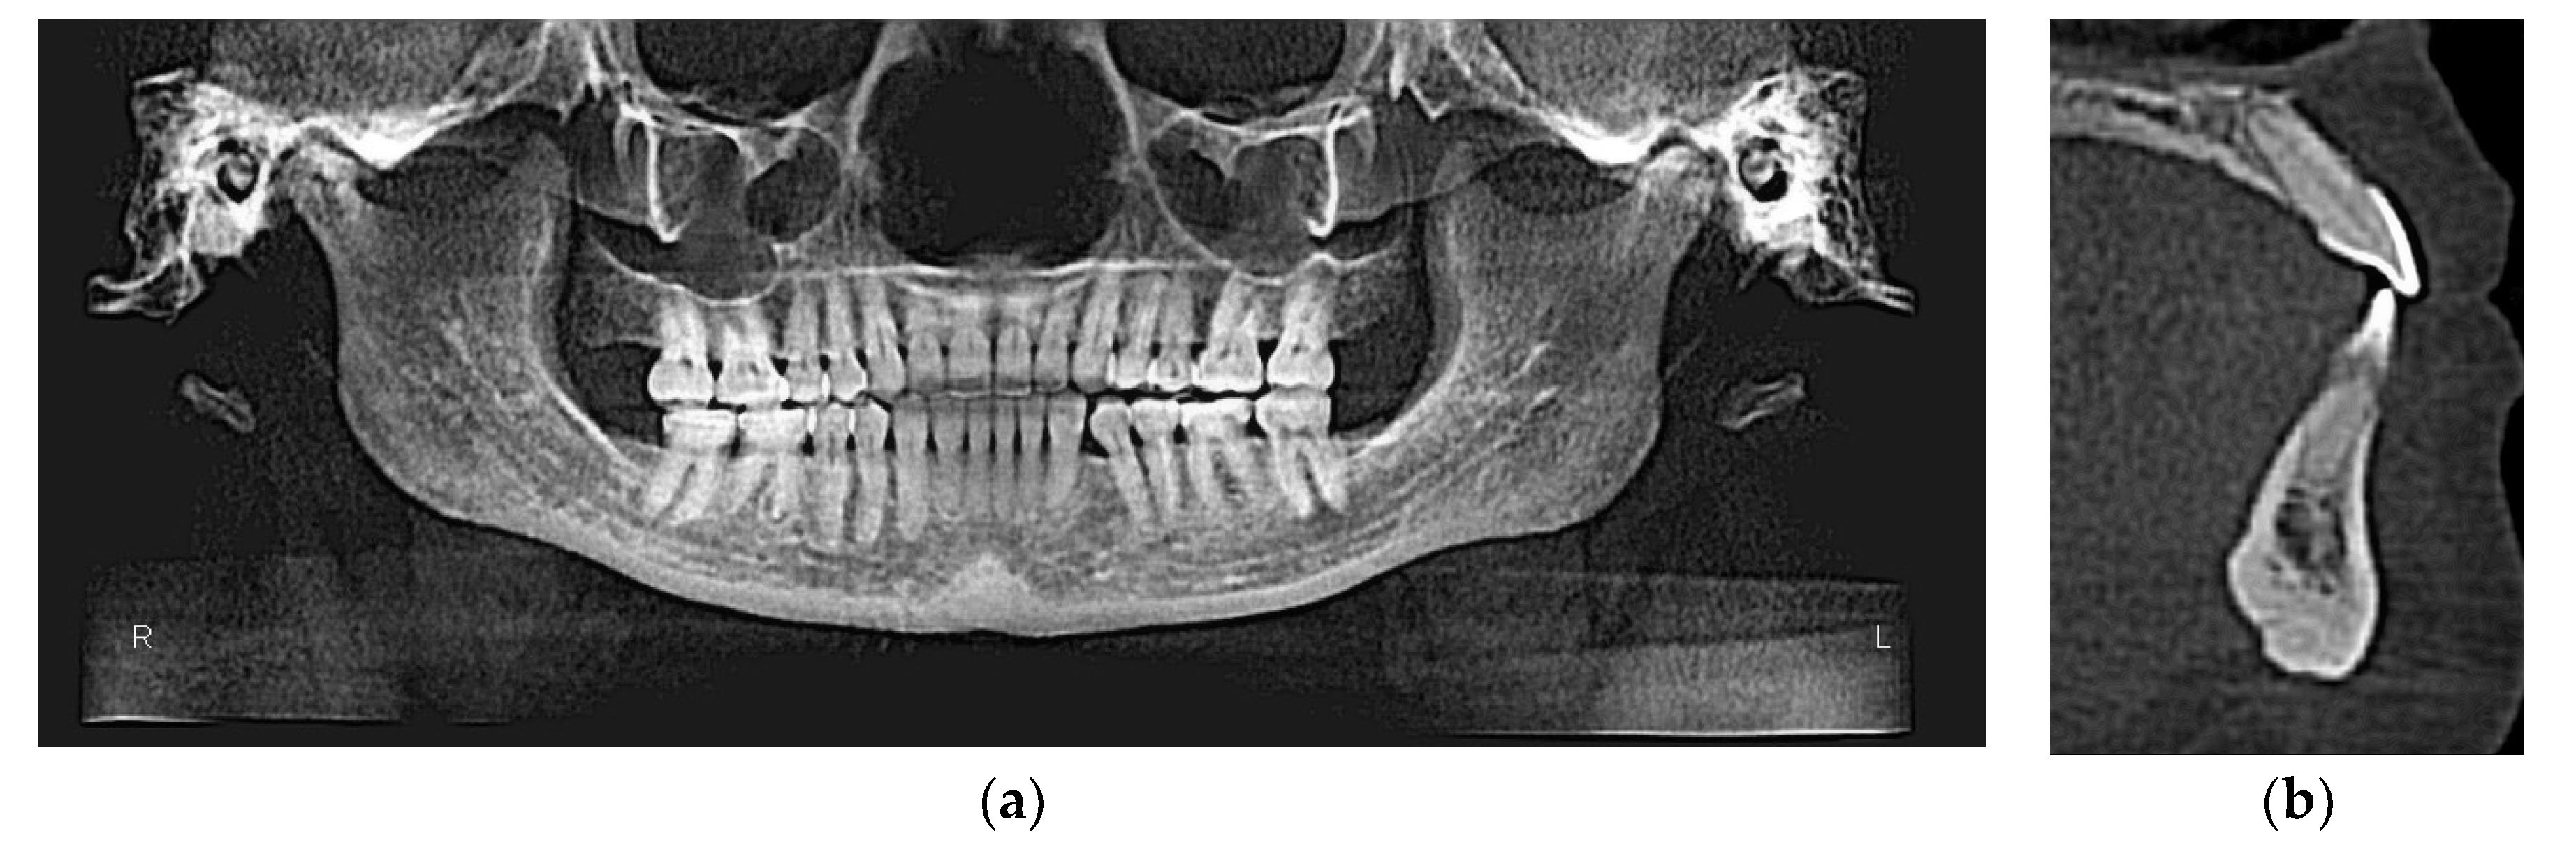

3.2. CBCT-Driven Radiographs

3.2.2. Panoramic and Sagittal Screen Radiographs